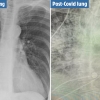

“어떤 흡연자보다 심각”…美 의사, 코로나19 환자 폐 사진 공개

[정기석의 환경과 우리몸] 코로나19로 인한 폐섬유화증 논란, 진실은

2020-08-18 서울신문 -